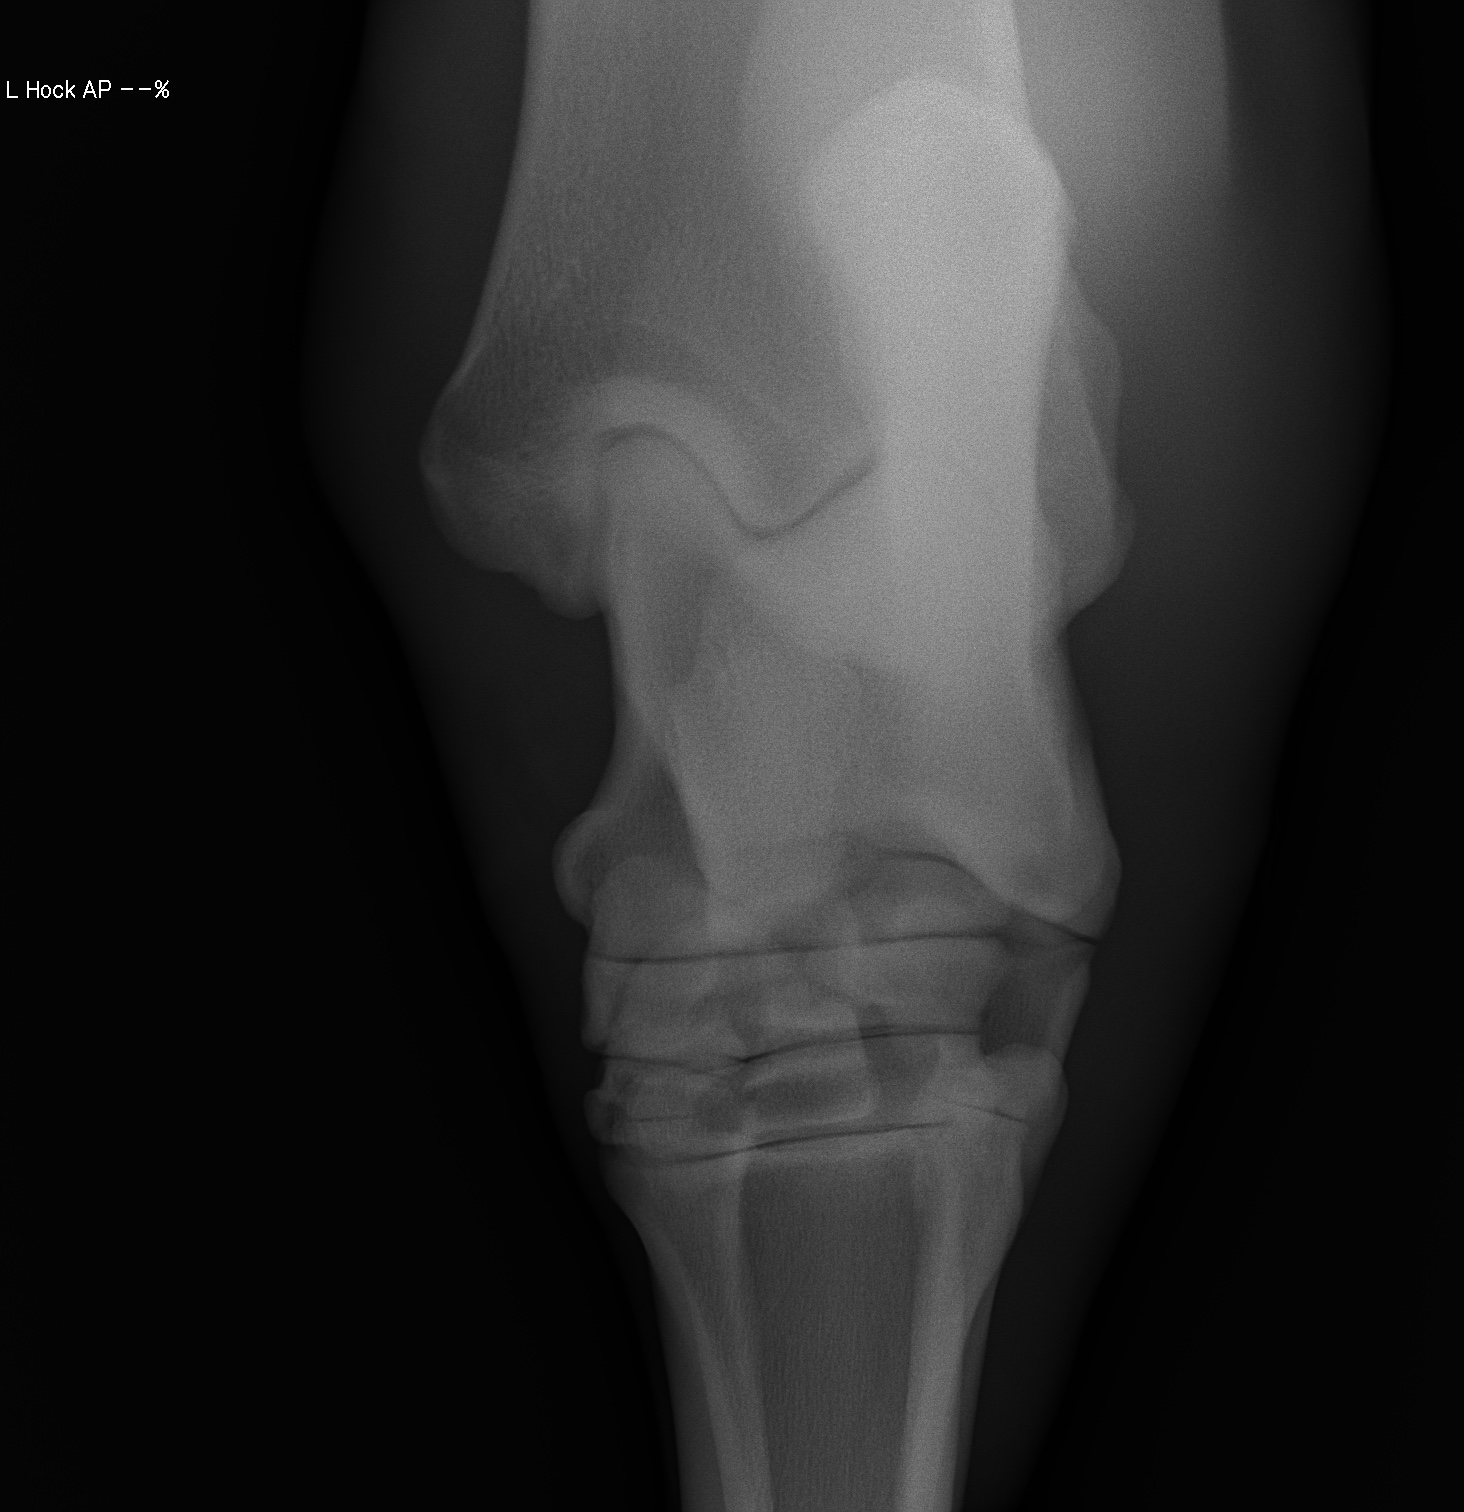

添付のレントゲン画像をご確認ください。現状渡しのノークレームノーリターンでお願いいたします。記載事項に関するキャンセルには応じられません。

前走で暴れた際にひねって、ヒビが入ってしまったのではないかと思われます。舎飼にて安静を保ち、時間を掛けて自然治癒を待つ他なく、早くても実戦復帰まで半年は要すでしょう。テンションのコントロール、ゲート枠内での駐立不良をなんとかしようと試行錯誤してアプローチしてみましたが、結果を出すことができませんでした。なお、興奮時にDDSP(軟口蓋背方変位)のような症状をみせることがあります。(船橋競馬・佐藤裕太調教師)

※2022年12月17日の競走にて左後脛骨不全骨折を発症しています(全治6~9ヵ月)。